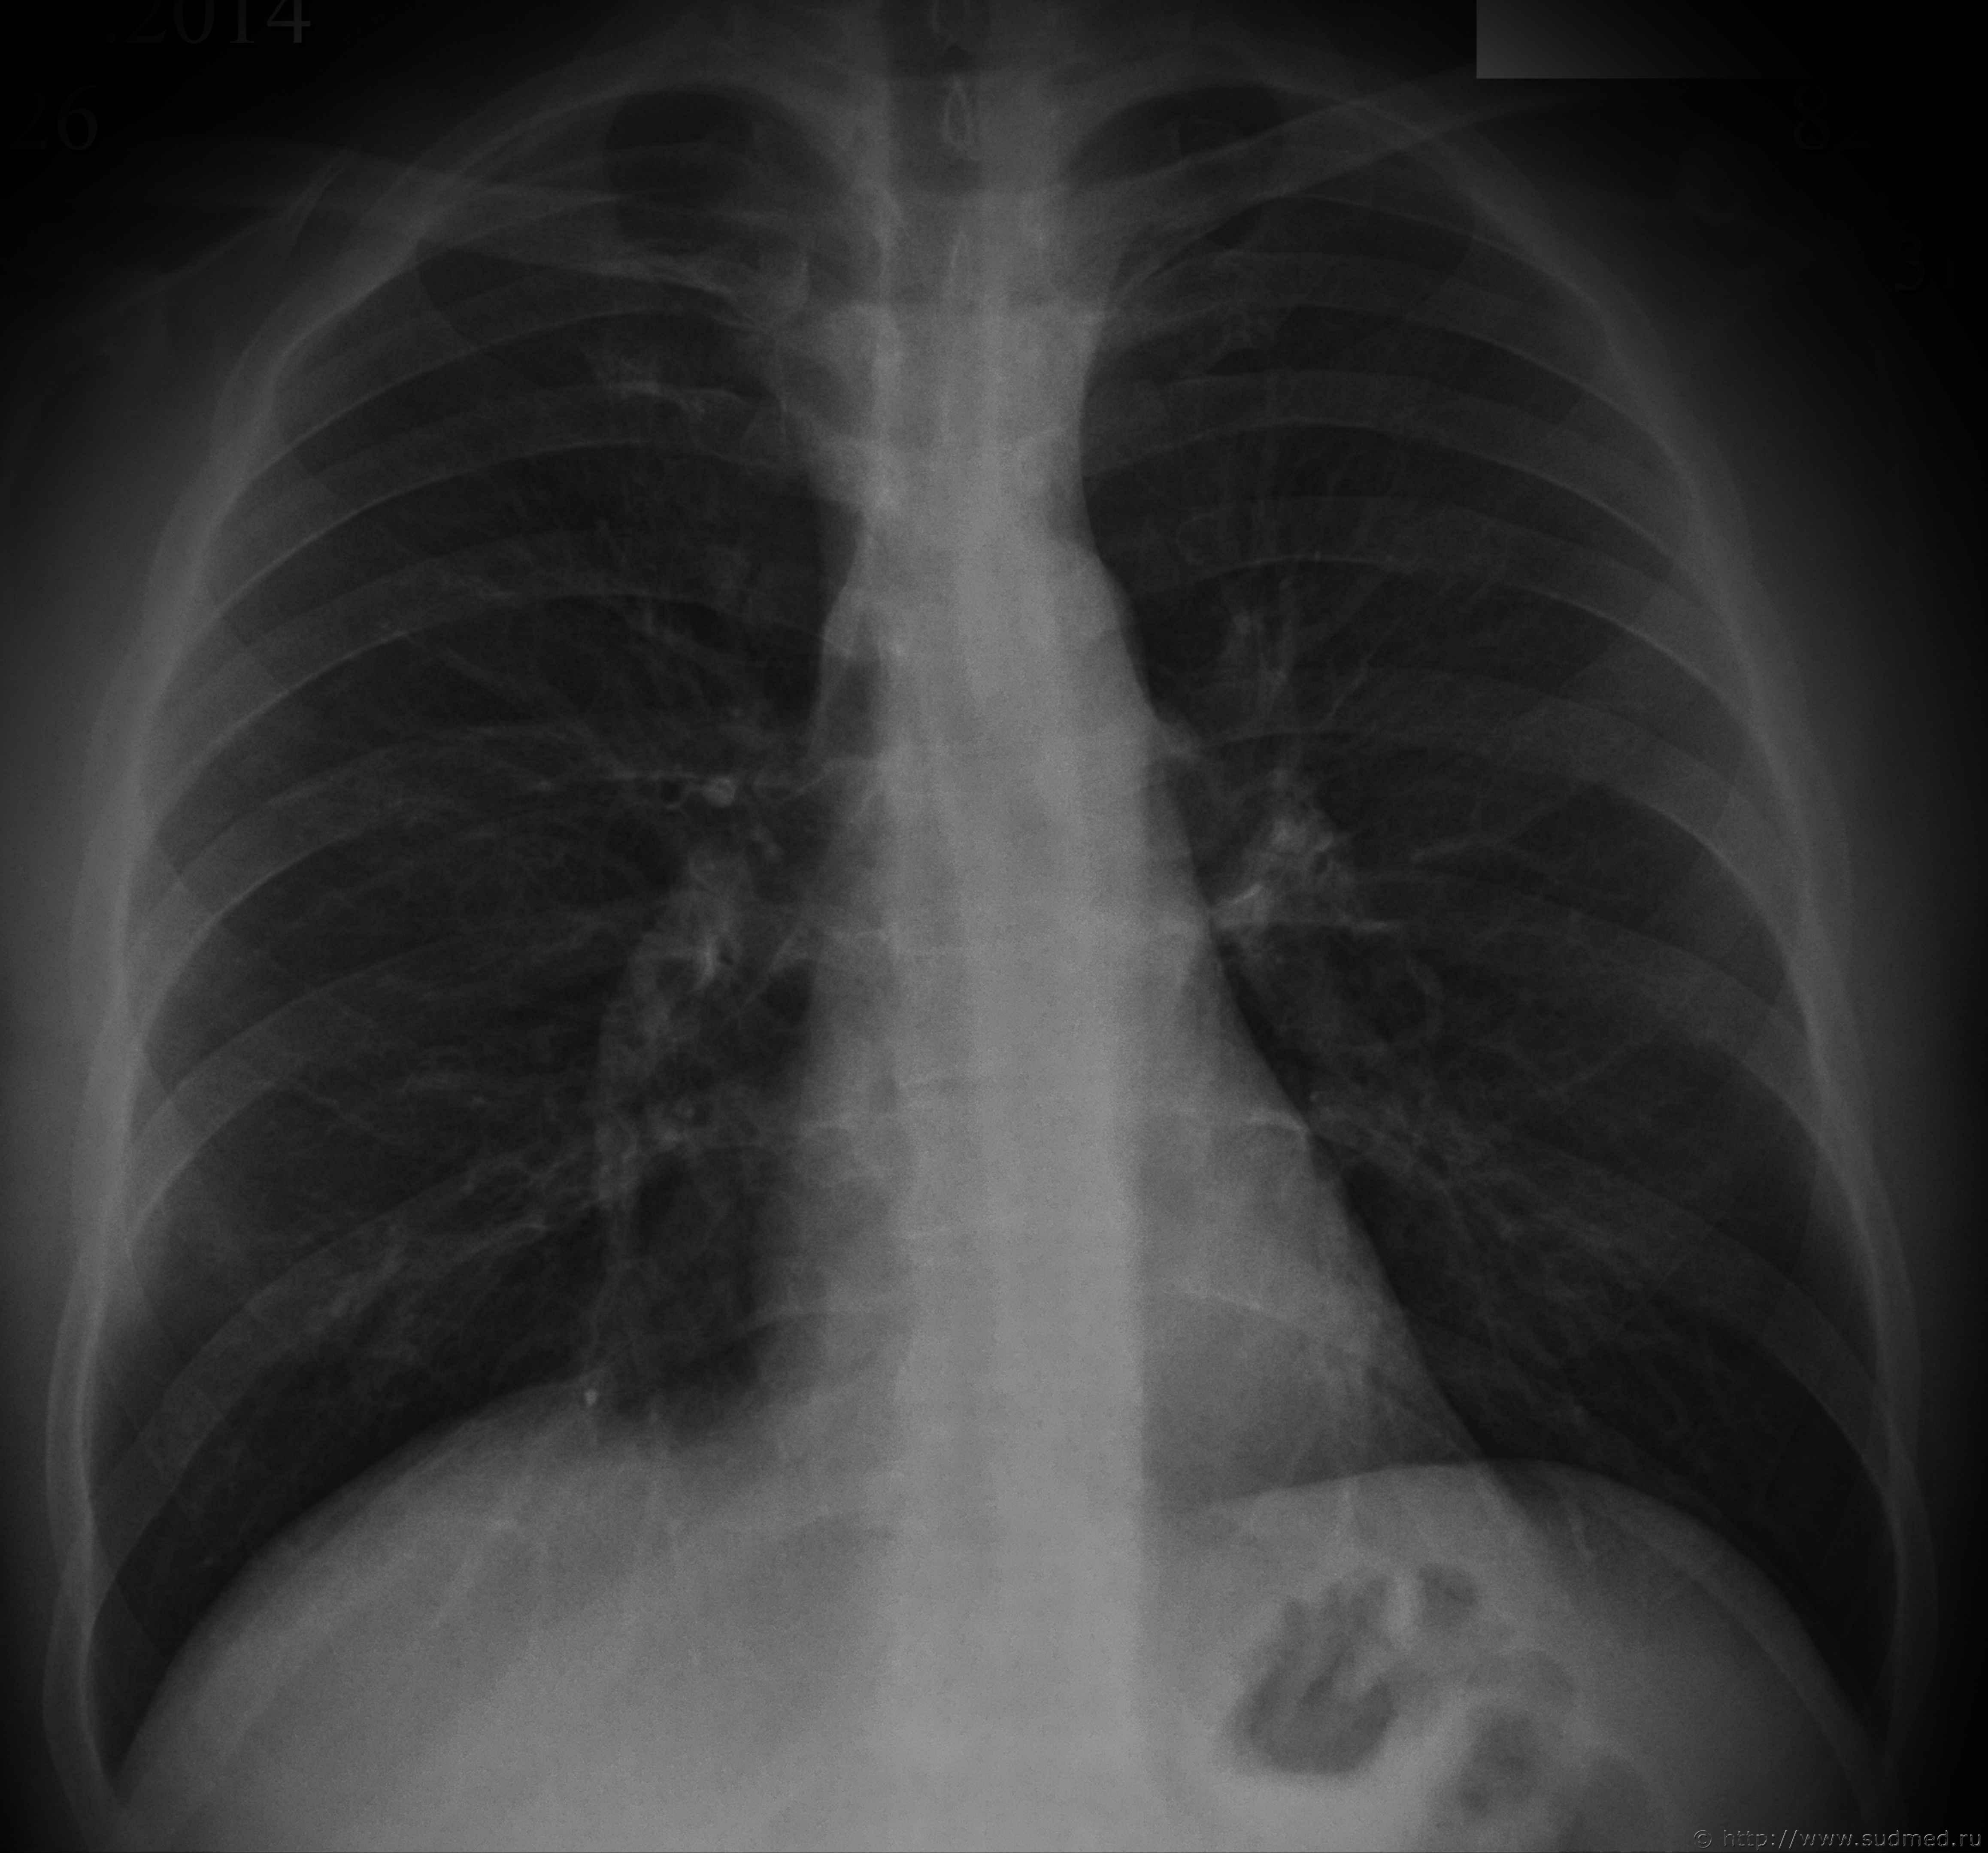

Некоторое время назад проводил экспертизу, у потерпевшего были переломы 8-10 ребер справа, ожидается что, может возникнуть вопрос по давности их образования, прикладываю предоставленные мне рентгеновские снимки. Какие мнения?

Изменений 8 и 10 ребер не вижу. Оч.похоже на посттравматическую деформацию (консолидированный перелом) 9 правого ребра между лопаточной и задней подмышечной линиями. Незначительная сглаженная "штыкообразная" деформация по верхнему и нижнему контурам ребра. Ступенеобразной деформации нет. Перерыва контура нет. Линия перелома не прослеживается. Костная структура восстановлена.

Если снимки сделаны на протяжении нескольких недель или более, то появляется еще один аргумент за давний перелом - отсутствие рентгенологических признаков динамики процесса (нет резорбции краев перелома и "расширения" его рентгенологической щели, нет появления и динамики костной мозоли).

Если же рентгенограммы сделаны относительно одномоментно (менее трех недель от даты предъявляемой травмы) и вопрос очень принципиален, то можно выполнить контрольные рентгенограммы: 1.правой половины грудной клетки в задней прямой проекции, 2.с выведением области интереса (вышеназванного изменения ребра) в краеобразующую зону. Тогда все станет еще более очевидно.

На 9-м ребре справа по задней подмышечной линии имеется участок деформации - но "свежих" переломов я не вижу... А так как на обоих снимках в прямой проекции этот участок в тени другого ребра (передних отделов) - я вообще не стал бы заморачиваться - написав об отсутствии "свежих" костно-травматических изменений.

Свежих переломов нет. Даже на счёт консолидированных - сомнительно, но полностью не исключаю (например, заживление перелома без смещения, либо не полного перелома). Как вариант, ходатайствовать копам о проведении КТ.